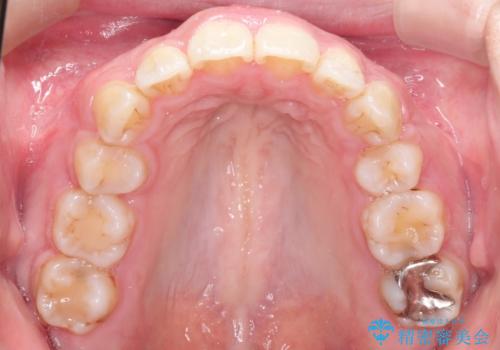

- 歯並びがガタガタなのと、口が閉じずらいのを主訴に来院されました。

上下左右の歯を1本ずつ、合計4本抜歯して、ワイヤー矯正を行うこととなりました。

右上の歯は、歯並び的には前から4番目の歯を抜歯したかったのですが、5番目の歯がすでに治療してある歯でしたのでこちらの歯を抜歯しました。

これにより少し治療期間が延びてしまいましたが、健康な歯を残すことができました。